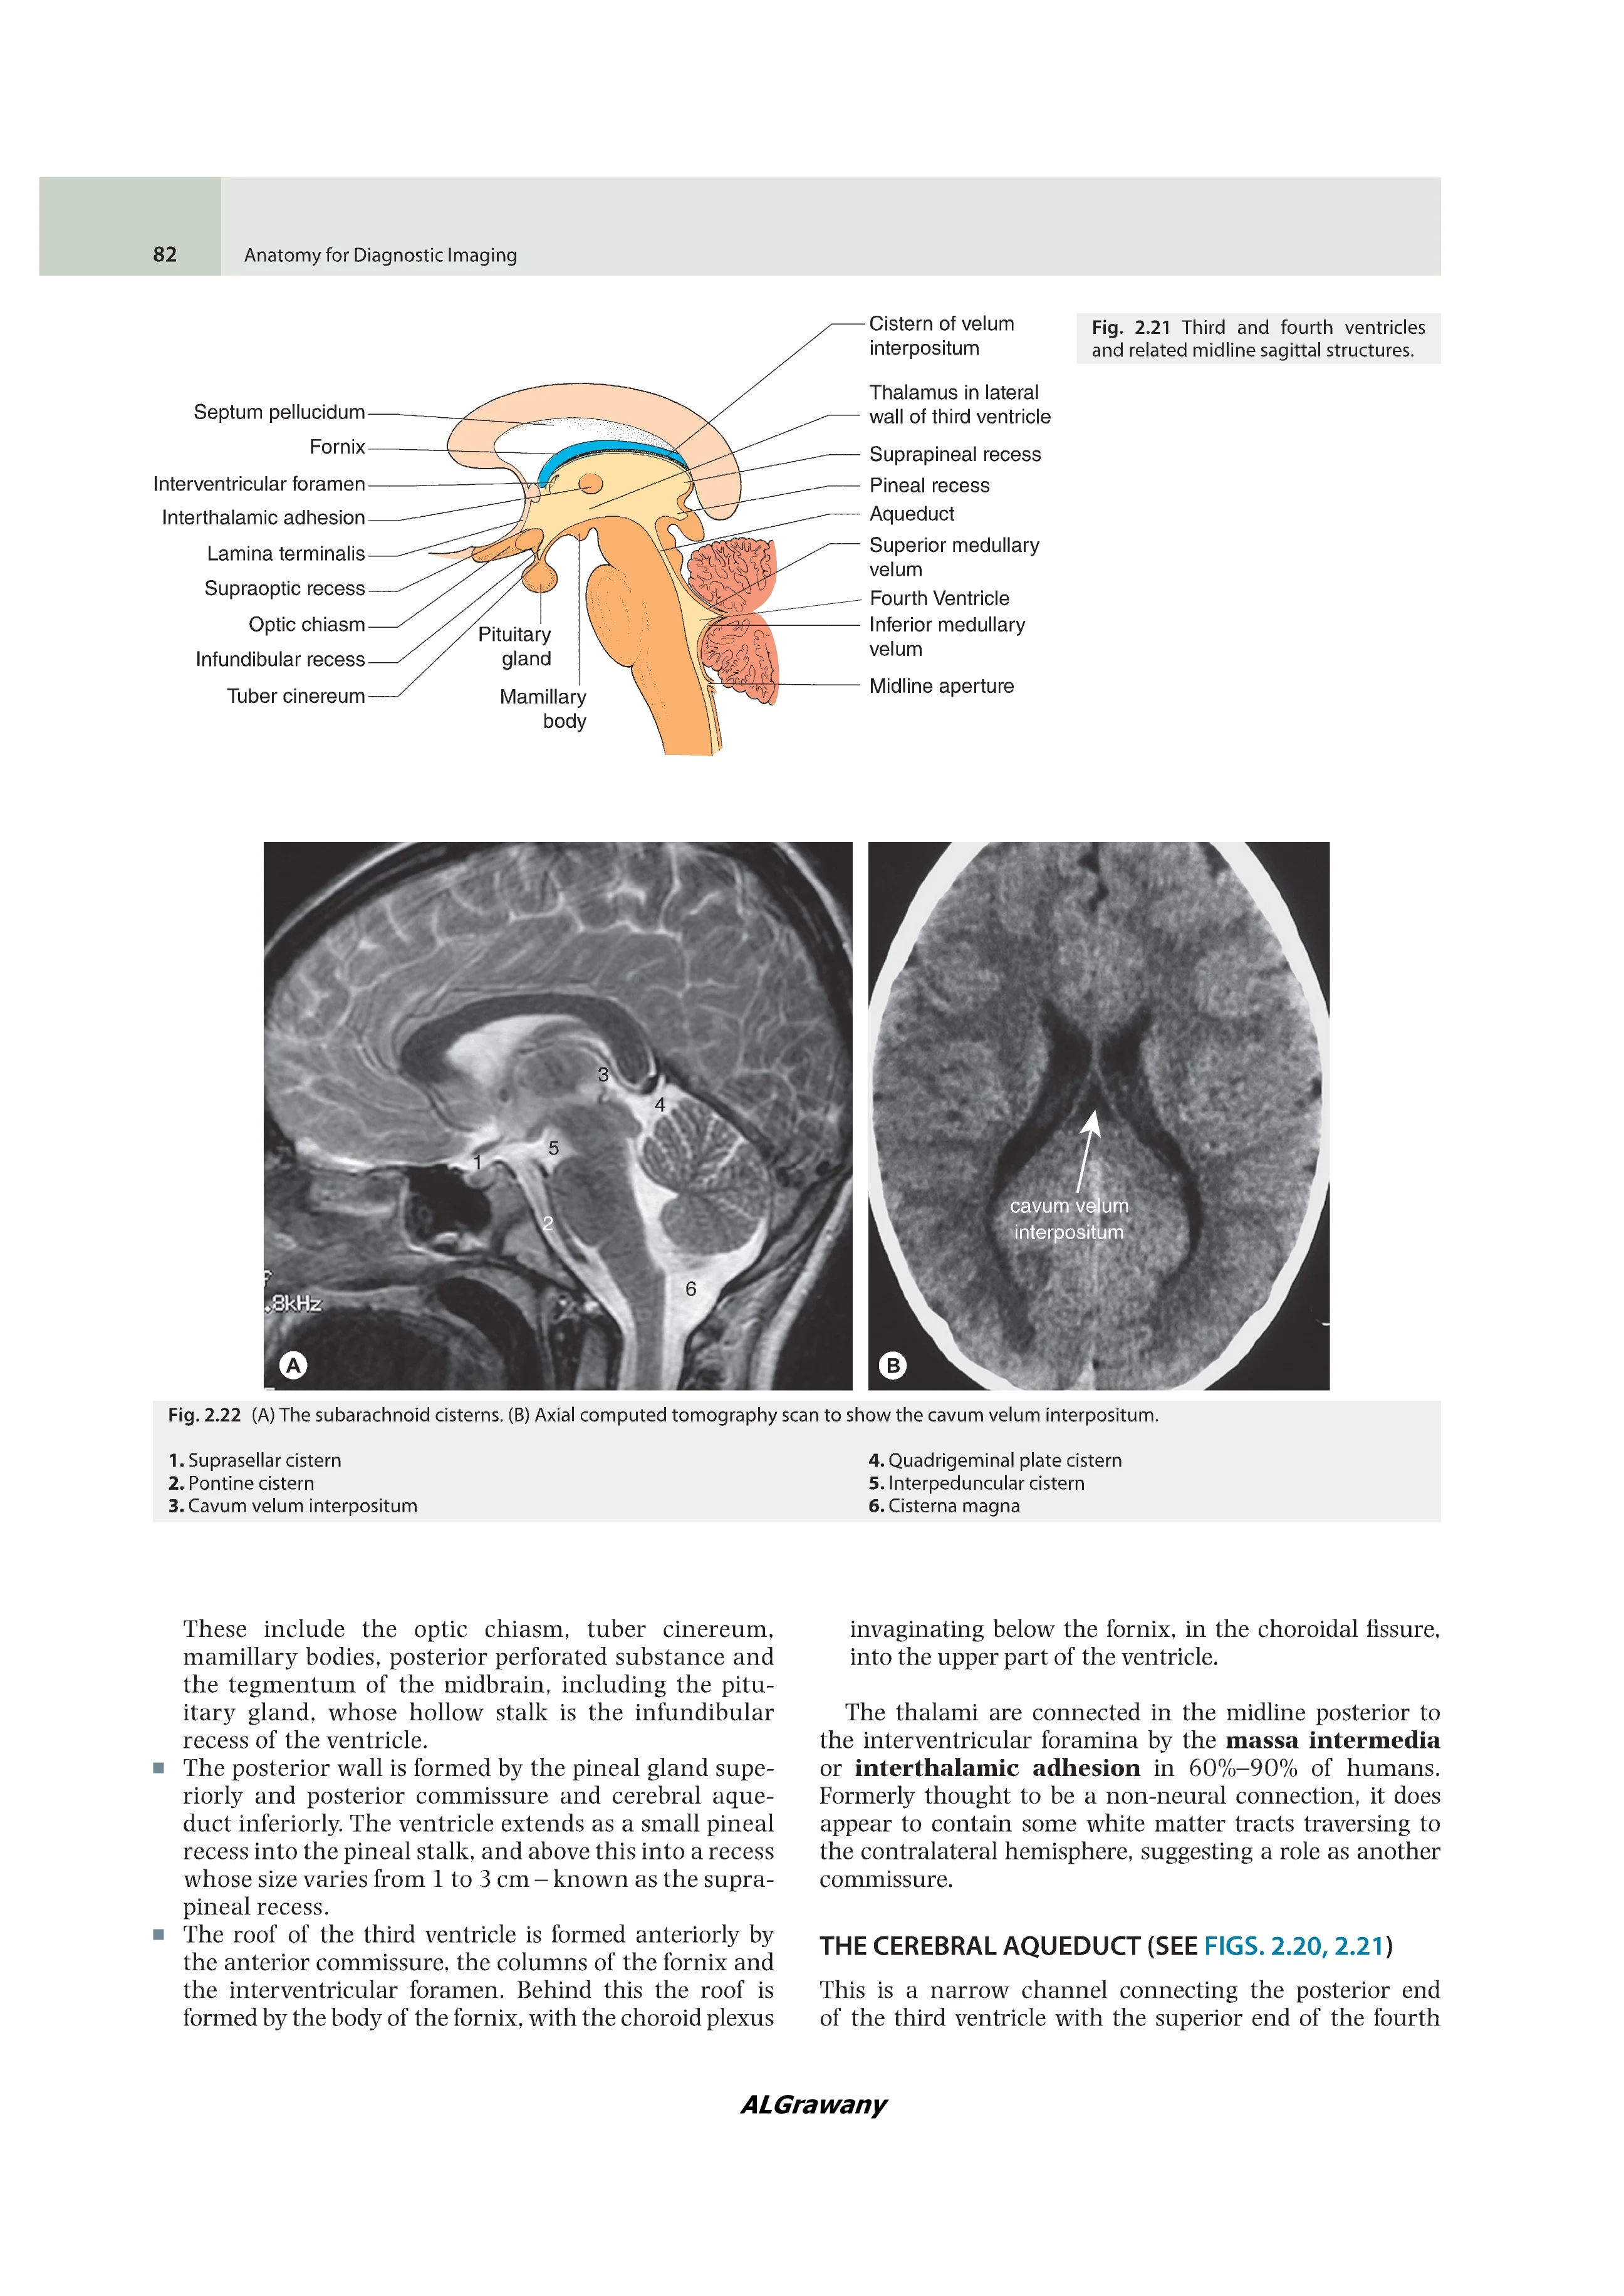

Иллюстрации: Цветные и черно-белые

Anatomy for Diagnostic Imaging, Fourth Edition covers everything trainee radiologists need to know about anatomy shown in the full range of medical imaging, including CT, MR and ultrasound.

It provides an initial traditional anatomical description of each organ or system, followed by the radiological anatomy of that part of the body with labelled imaging examples in all modalities. A series of 'radiology pearls' emphasises clinically and radiologically important points.

Written by radiologists with immense clinical and teaching experience, with seven new contributors, the fourth edition has been fully updated reflecting advances in imaging and evolving clinical practice. It will be indispensable for radiology registrars and residents, especially candidates for postgraduate radiology exams. A manageable size, it will also be of great use to radiographers, medical students, physicians, surgeons and others whose work requires an understanding of radiological anatomy. It is also an extremely useful reporting station reference book.

Provides key images in all modalities